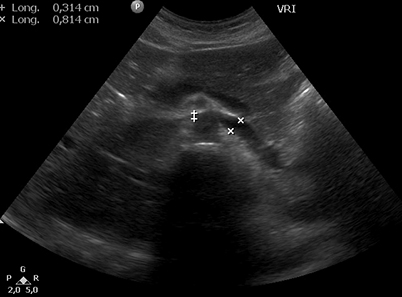

Fig. 3. Examen ecográfico abdominal, se observa compresión de la vena renal izquierda entre la aorta y la arteria mesentérica superior (mide 3,1 mm a nivel del compás y 8,1 mm en el segmento proximal al riñón izquierdo).

Hallazgos imagenológicos. En el eco Doppler ginecológico por vía transvaginal se observa varicocele pelviano (Fig. 1). La vena ovárica derecha mide 3.8 mm, y la izquierda, ectásica, 7.4 mm (Fig. 2). En el eco Doppler abdominal se visualiza la vena renal izquierda, de 3.1 mm en topografía del compás aorto-mesentérico y 8.1 mm en el segmento proximal al riñón izquierdo, con una velocidad 50cm/s en el compas y 30cm/s en el segmento proximal al riñón. El estudio corresponde en primera instancia a un síndrome de Nutcracker (Fig. 3).